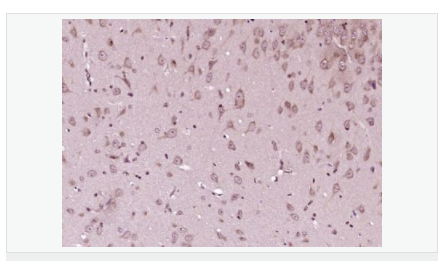

產(chǎn)品應(yīng)用WB=1:500-2000 ELISA=1:5000-10000 IHC-P=1:100-500 IHC-F=1:100-500 Flow-Cyt=1μg/Test ICC=1:100-500 IF=1:100-500 (石蠟切片需做抗原修復(fù))

細(xì)胞定位細(xì)胞核 細(xì)胞漿

P27蛋白是一種新發(fā)現(xiàn)的周期素依賴激酶抑制劑,屬于細(xì)胞周期的負(fù)性調(diào)控因子。P27基因及其產(chǎn)物的異常表達(dá)可能與某些腫瘤的發(fā)生、發(fā)展有著密切的關(guān)系。P27蛋白對細(xì)胞周期的調(diào)控及在腫瘤中發(fā)揮著很重要的作用。